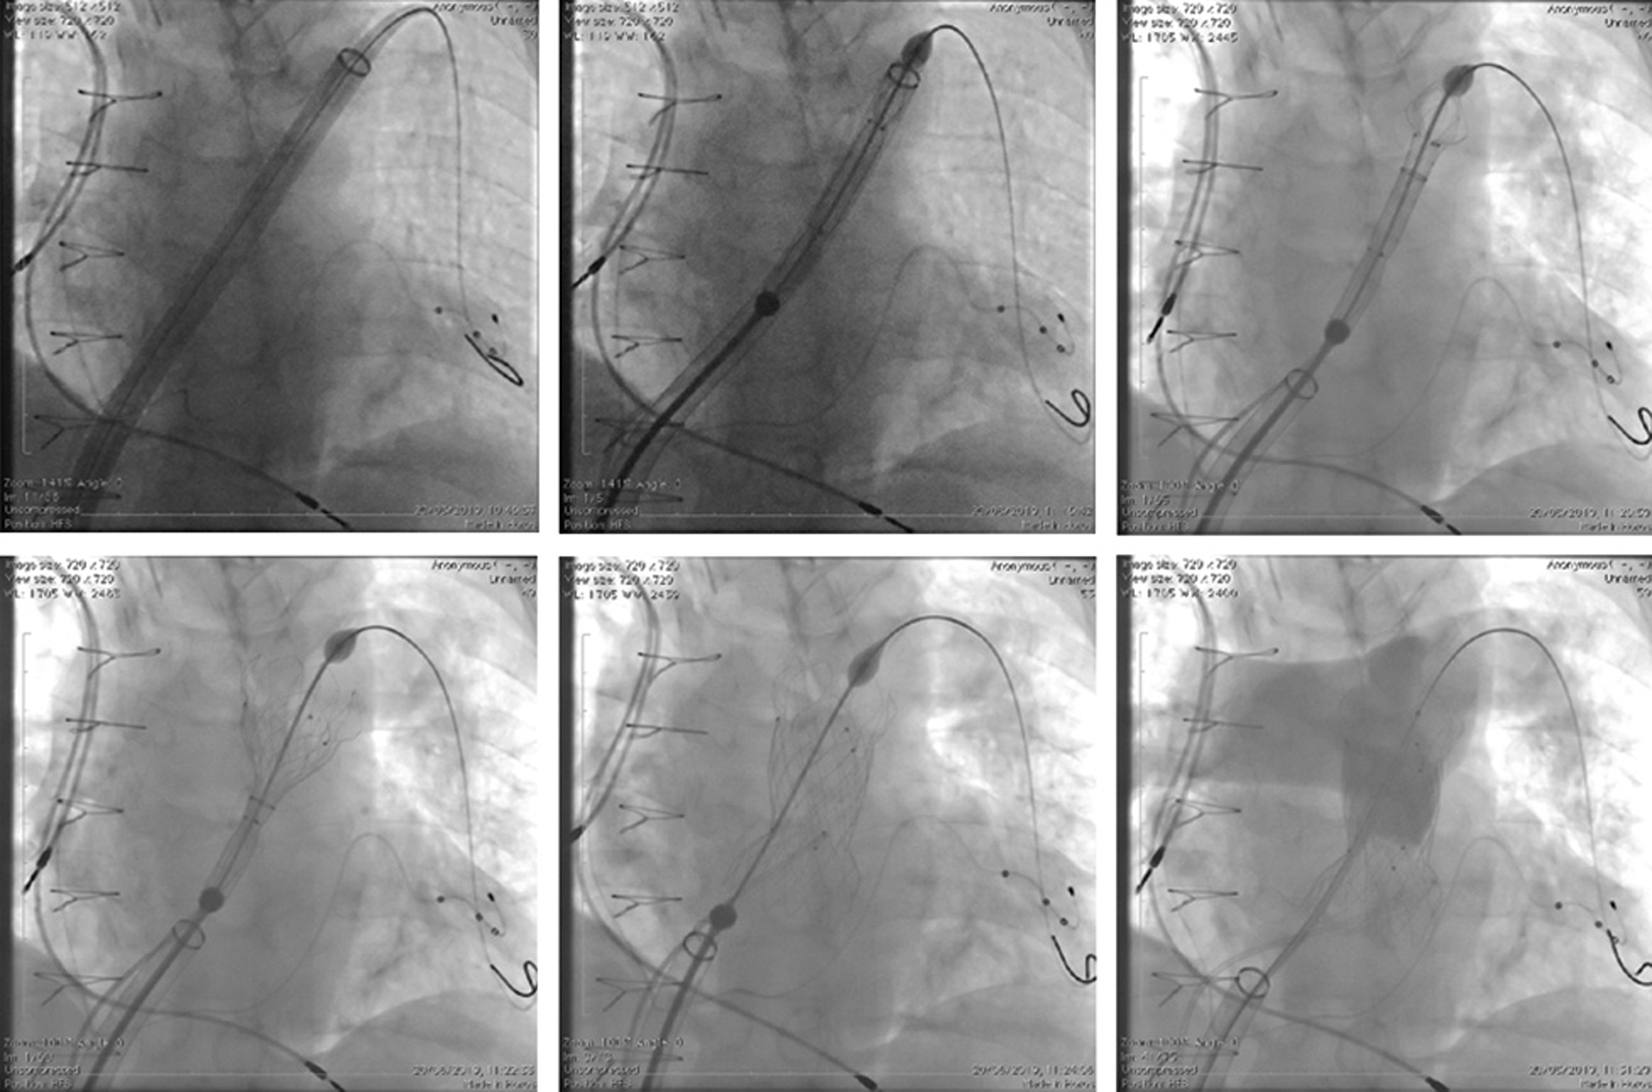

All the procedures were performed under general anaesthesia. Femoral vein access was obtained using ultrasound guidance in five patients and using anatomical landmarks in seven patients. After obtaining satisfactory wire position in the distal left pulmonary artery using a 0.035” Lunderquist guidewire (Cook Medical, Bloomington, IN, USA), the vein was serially dilated and the GORE® DrySeal sheath inserted. A 65 cm long 26F GORE DrySeal sheath was used in the GORE® DrySeal group. The distal end of the sheath was advanced to the proximal LPA in 7 patients and in the distal main pulmonary artery (MPA) in 5 patients. In the patient with the previously implanted LPA stent, the stent was predilated in order to facilitate passage of the sheath to the LPA. The Venus P-valve was crimped onto the delivery system using the previously described technique [3–7] and inserted over the distally placed wire through the GORE® DrySeal sheath to the distal position while opening the proximal “valve” system (Fig. 2). The GORE® Dryseal sheath was then withdrawn to uncover the valve and deployed in the usual fashion in the RV outflow [3–7] (Fig. 2).

Figure 2: Fluoroscopic AP view showing the steps of the Venus-P valve implantation